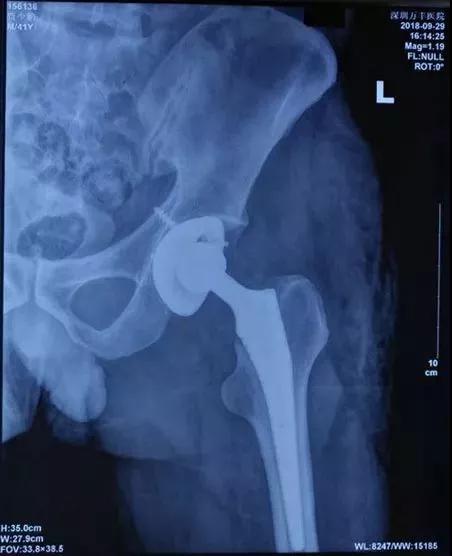

在骨科蔡炎泉、白香彪等医生的配合下,全体医护人员通力协作,1小时、2小时、3小时、4小时......根据多年团队配合的经验和手术技巧,终于,贾先生的新“关节”被精心安放在恰当位置,髋关节全髋置换手术顺利完成!

▲病患部位术后DR照